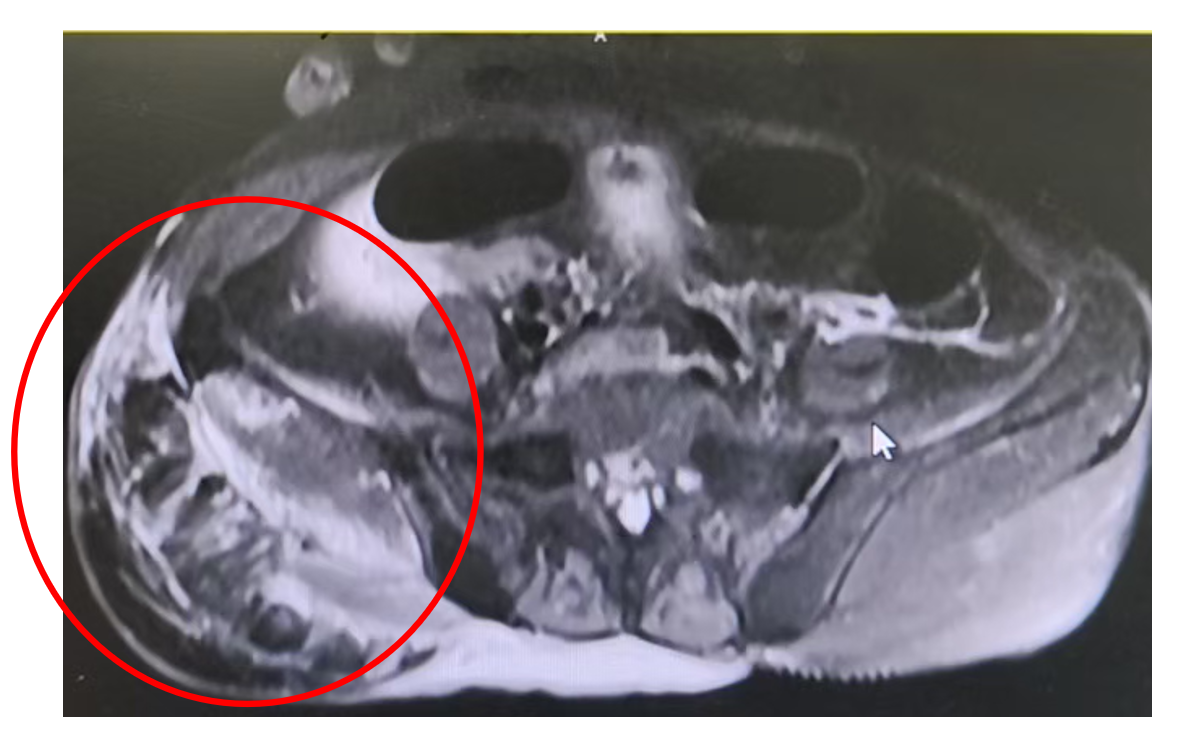

患者女,84岁,主诉:右髋部疼痛5天。现病史:5天前右髋部疼痛伴活动受限,伴右大腿肿胀,可见大片皮下瘀斑,皮温稍高,压痛。血常规示血红蛋白61 g/L;凝血功能:APTT 58.3秒;凝血因子Ⅷ活性 3.6%。双髋CT示右髋部软组织肿胀、紊乱,臀中肌为甚,考虑出血并血肿形成可能性大。MR示右髋关节周围软组织异常信号影。右髋部疼痛逐渐加重至我院就诊,拟“凝血功能障碍”收治我科。家族史:否认血友病等其他出血性疾病病史。

专科检查:患者呈贫血貌,四肢及背部可见大片瘀斑,右大腿肿胀、活动受限,局部皮温升高,压痛阳性。

入院后给予患者制动、止痛、哌拉西林/舒巴坦抗感染及成分输血支持。止血治疗方面,考虑患者皮肤黏膜及肌肉出血范围广、量大且进展迅速,需积极干预,遂予以rFVIIa总量4000 μg,并联合凝血酶原复合物1500 U q12h。同时予以免疫抑制治疗以清除FⅧ抑制物。

万军教授:患者因大面积瘀斑及右大腿肿胀入院,确诊为获得性血友病A。临床主要表现为皮肤黏膜及肌肉大面积出血,出血范围广泛、量大,病情进展迅速,需立即止血干预。治疗过程中予以rFⅦa(共4000 μg)联合凝血酶原复合物进行止血。患者瘀斑逐渐消退,血肿逐步吸收,肿胀与疼痛明显缓解。实验室复查显示APTT逐渐恢复正常,FⅧ活性显著升高,抑制物滴度持续下降。整体治疗效果理想,患者病情明显改善并恢复良好。